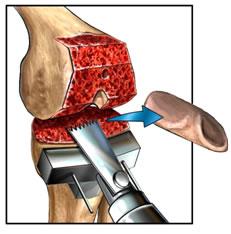

Once the anaesthesia has been given and the patient prepared an incision approximately eight cm in length is made on the front of the knee. The surrounding muscles and most of the ligaments are cut in such a manner that they can be preserved. The damaged bone and joint surfaces are removed from all 3 bones making up the knee joint. Sometimes, depending on the surgeon, the back of the knee cap is left intact if it is not badly affected by the arthritis.

The lower end of the thigh bone (femur) is resurfaced with a metal cap.

The upper end of the leg bone (tibia) is replaced with a plastic and metal implant with cement and or screws.

The back of the kneecap (patella) is also resurfaced with an all-plastic implant. Highly specialized instruments are used that allow precision cutting of the bone so that the new joint fits perfectly. The type of implant used depends on surgeon's preference and patient requirements.)